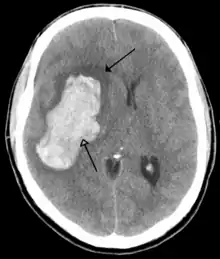

![]() | |

CT scan of the brain showing a prior right-sided ischemic stroke from blockage of an artery. Changes on a CT may not be visible early on.[1] | |

The biggest risk factor for stroke is high blood pressure.[7] Other risk factors include high blood cholesterol, tobacco smoking, obesity, diabetes mellitus, a previous TIA, end-stage kidney disease, and atrial fibrillation.[2][7][8] Ischemic stroke is typically caused by blockage of a blood vessel, though there are also less common causes.[13][14][15] Hemorrhagic stroke is caused by either bleeding directly into the brain or into the space between the brain's membranes.[13][16] Bleeding may occur due to a ruptured brain aneurysm.[13] Diagnosis is typically based on a physical exam and supported by medical imaging such as a CT scan or MRI scan.[9] A CT scan can rule out bleeding, but may not necessarily rule out ischemia, which early on typically does not show up on a CT scan.[10] Other tests such as an electrocardiogram (ECG) and blood tests are done to determine risk factors and rule out other possible causes.[9] Low blood sugar may cause similar symptoms.[9]